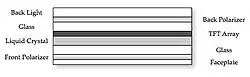

An LCD is a two-dimensional, electro-optical light modulator that is mounted in front of a back-light - see Figure 6.1. The light is modulated for each pixel by applying an electric field to a thin layer of nematic liquid crystal mounted between two polarising films. Active Matrix Liquid Crystal Displays (AMLCDs) apply the electric field to each pixel using a large array of Thin Film Transistor (TFT) switches made from amorphous silicon (a-Si) deposited on a glass substrate.

Components of a medical-grade LCD are shown in Figure 6.1.5. Here the LCD sandwich is shown in the top right photo, the back light consisting of fluorescent strips in the bottom left (note that the diffusing layer has been removed) and the LCD active layer in the bottom right. The device contains a small photodetector at the faceplate (not shown) which is used to maintain the brightness of the displayed image, and an ambient light sensor.